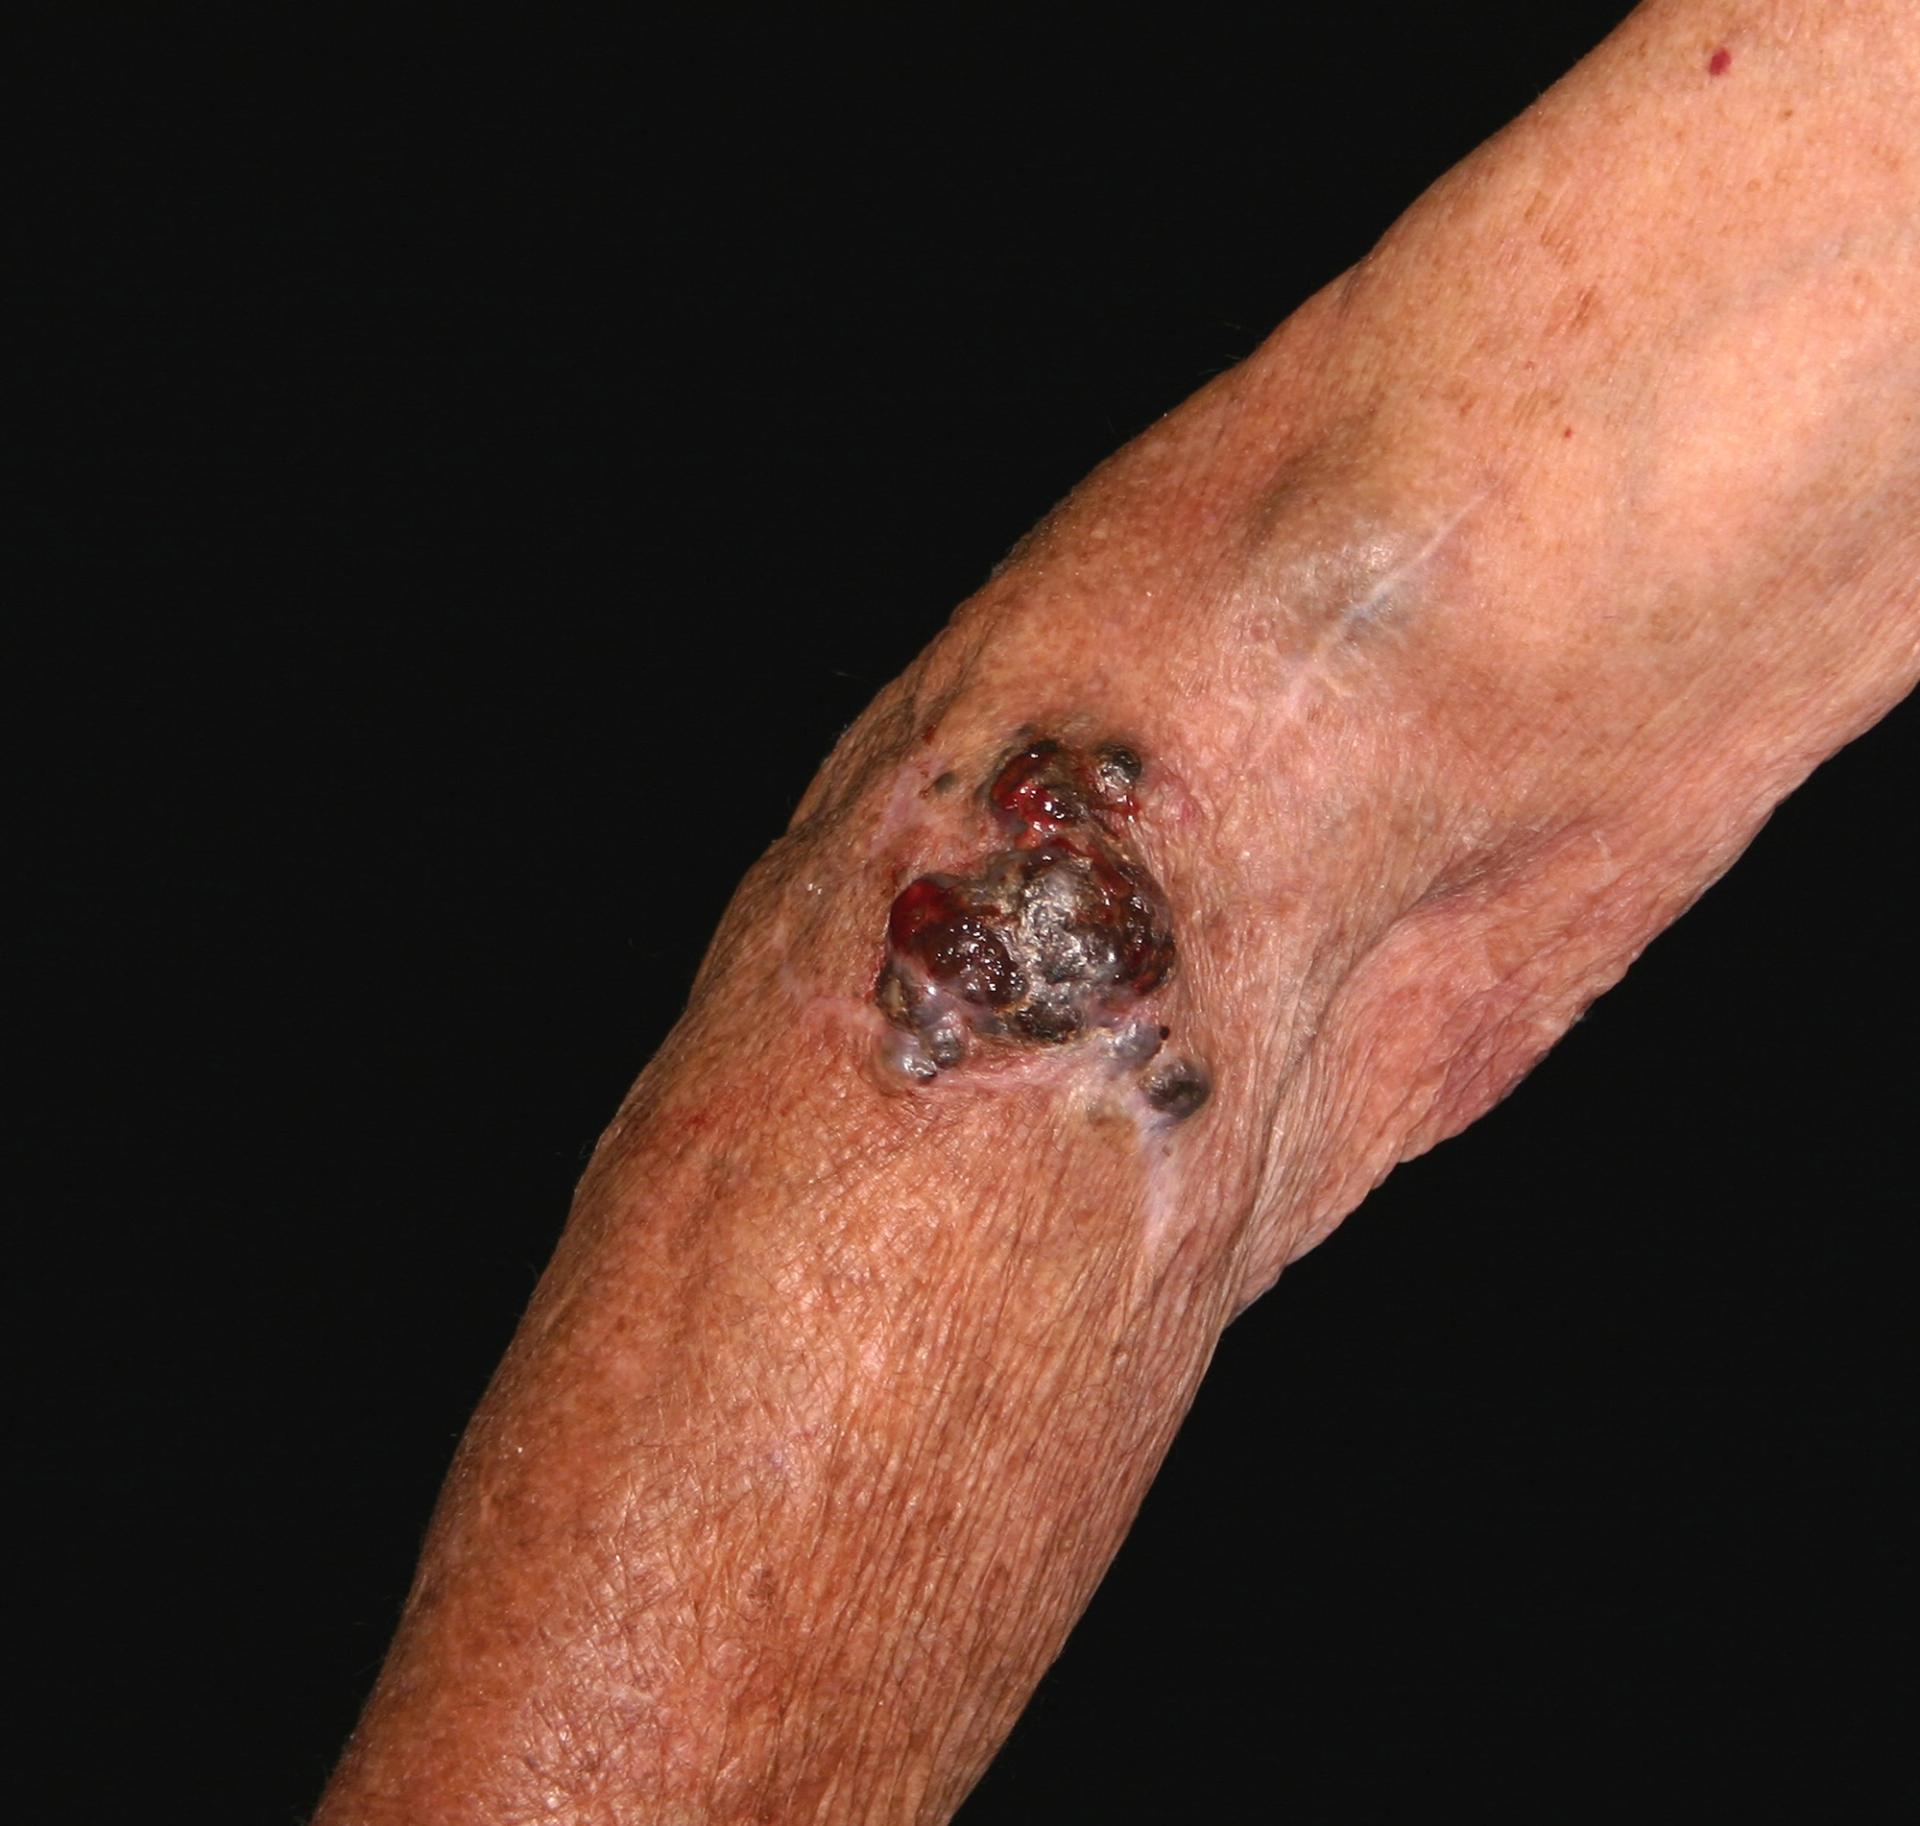

In the case of melanoma, this phase is relatively easy because melanoma has received a lot of attention over the last 40 years, as the increase in foreign package holidays has contributed to an increase in incidence: all types of skin cancer are related to sun exposure, and uniquely, malignant melanoma appears related to episodes of sunburn.4 The process starts when a patient presents to primary care with a mole that they are concerned about.

NICE Clinical Knowledge Summaries (CKS) currently recommend the use of a 7-point checklist (Box 1). A major feature scores 2 points and a minor feature scores 1 point. Anyone with a score of 3 or more should be referred under the ‘Two Week Wait’ protocol, usually to a dermatologist.5 There is a proviso, however, that in situations of high suspicion even one major or minor feature should prompt referral – an obvious example would be when there has been a previous diagnosis of malignant melanoma. The checklist can also be used to reassure patients who probably do not have malignant melanoma.

Rarely a mole removed by a minor surgery procedure in primary care will, on histological examination, unexpectedly turn out to be a malignant melanoma (NICE does not recommended that suspected melanomas are routinely removed in primary care). In such cases, a diagnosis can be made straight away, but even so an urgent specialist referral will be made for confirmation and further treatment. More commonly a patient will present with a mole that they are concerned about, and this will prompt the referral.

At the hospital clinic, there will be an examination of your entire patient’s skin, not just the suspicious mole. People with a melanoma are more at risk of having another melanoma, and they may occur on less visible bits of skin, so it makes sense to do a comprehensive inspection. A dermatoscope may be used for this – a piece of equipment that looks like a magnifying glass or camera with a light. The dermatoscope will have a magnifying glass to see the lesion better (typically with a 10X magnification). Also there will be some method of reducing reflection from the skin – older versions used a liquid medium, but newer models overcome this problem by using a polarised light source. A photograph of the mole may be taken.

Next, arrangements will be made for the entire mole to be excised. Together with the mole, a cuff of skin that looks normal will also be removed with at least a 2mm margin, and also some underlying skin fat. This way the thickness of the mole can be determined, which is important for future treatment. The excised tissue is sent to the laboratory to be examined in detail. The wound is sutured.